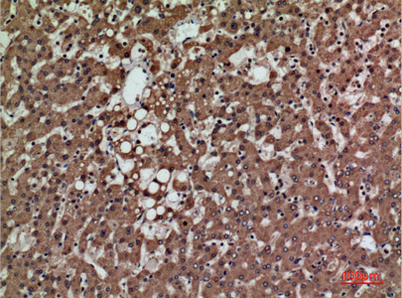

| Dilutions: | Western Blot: 1/500 - 1/2000. IHC-p: 1:100-300 ELISA: 1/20000. Not yet tested in other applications. |